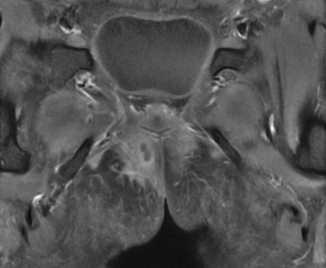

入院后第2日患者出现发热,体温最高39℃,无明显其他感染定位症状,抗生素治疗后仍有发热,复查hsCRP较前轻度升高(35.8mg/L~40.5mg/L),予抗感染治疗后高热仍反复。肛管MR增强检查显示“齿状线上方水平,约10~11点位置条片影经内外括约肌向右前下会阴皮下走行,外口不明确,局部与阴道紧贴,是否相通不明确;约10~11点位置另一条于内外括约肌间隙向右后上走行向直肠下段,似相通”(图1)。

图1  肛管MR增强